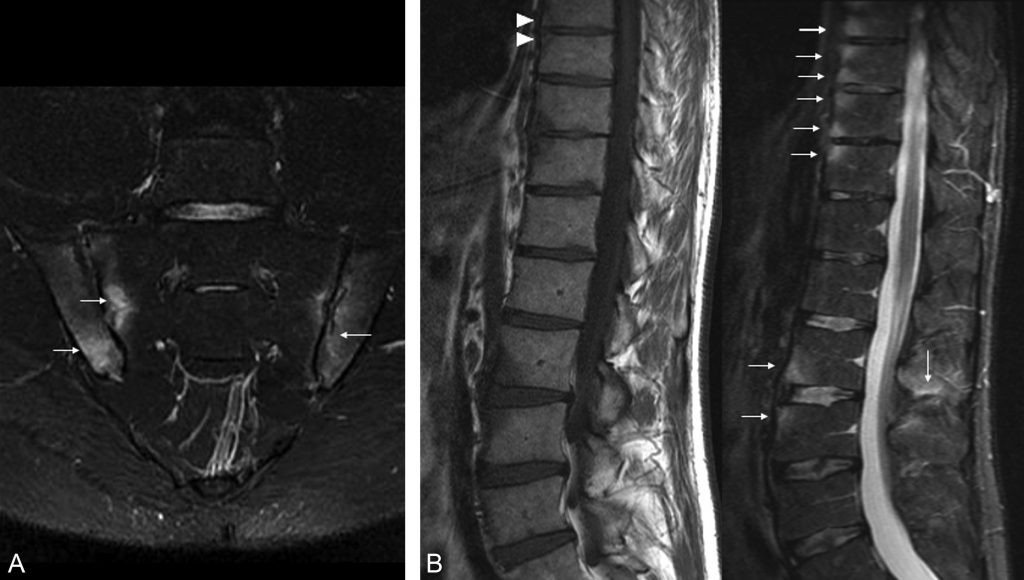

Fig. 84.2 Spondylarthrite ankylosante.

IRM des articulations sacro-iliaques (coupe coronale STIR) et du rachis thoracolombaires (coupe sagittale T1 et STIR) montrant un œdème (flèches) des berges des articulations sacro-iliaques, de plusieurs coins vertébraux antérieurs et d’un ligament inter-épineux. Notez la présence de coins vertébraux graisseux (têtes de flèche) témoignant de la conversion graisseuse de lésions préalablement inflammatoires.

Source : CERF, CNEBMN, 2022.